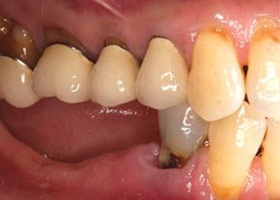

假牙完成照

因植牙恢復正常咬合